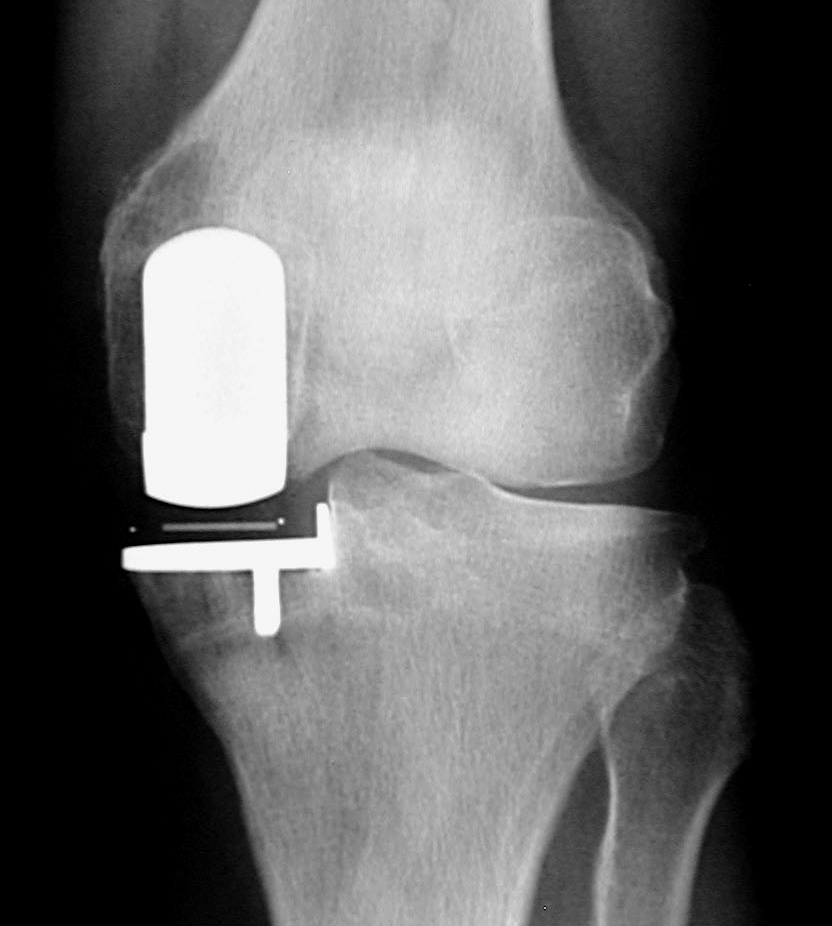

(“鑲牙”似的單髁置換術(shù)后X光片)

微創(chuàng)膝單髁置換術(shù)與全膝關(guān)節(jié)置換術(shù)相比,優(yōu)勢(shì)十分明顯。微創(chuàng)膝單髁置換術(shù)具有手術(shù)切口小,損傷小,出血少,無(wú)需輸血;術(shù)后疼痛少,術(shù)后第2天即能下地行走,術(shù)后3天可以出院。2017年6月以來(lái),柳州市人民醫(yī)院關(guān)節(jié)骨病運(yùn)動(dòng)醫(yī)學(xué)科以彭偉秋博士為首的團(tuán)隊(duì),積極學(xué)習(xí)和引進(jìn)新技術(shù),在柳州市率先成功開展了膝關(guān)節(jié)單髁置換手術(shù)。柳州380萬(wàn)人口中20%是60歲以上老人,76萬(wàn)老人中約有50萬(wàn)老人患有老年性膝骨性關(guān)節(jié)炎,其中3%是處于晚期。由于晚期老年性膝骨性關(guān)節(jié)炎致殘,病人無(wú)法生活自理,給家庭和社會(huì)帶來(lái)了較重的負(fù)擔(dān)。我院開展的微創(chuàng)膝單髁置換術(shù)實(shí)現(xiàn)了對(duì)晚期膝骨性關(guān)節(jié)炎的精準(zhǔn)優(yōu)化治療,具有康復(fù)快,療效優(yōu),病人樂(lè)意接受等特點(diǎn),為保障老百姓的健康提供了新方案。